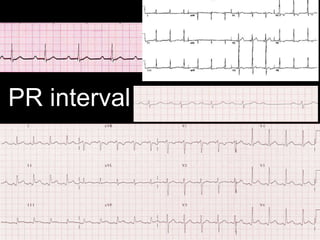

PR interval

1˚HB

Lown-Ganong-Levine syndrome

with short PR interval

Mobitz type 2 2˚HB

• #23 1˚ HB eg rheumatic fever, short PR in Lown-Ganong-Levine syndrome, PR depression (and elevation in aVR) in pericarditis. Mobitz 1 = Wenckeback. TP segment is the baseline.

• #24 1˚ HB eg rheumatic fever, short PR in Lown-Ganong-Levine syndrome, PR depression (and elevation in aVR) in pericarditis. Mobitz 1 = Wenckeback. TP segment is the baseline.